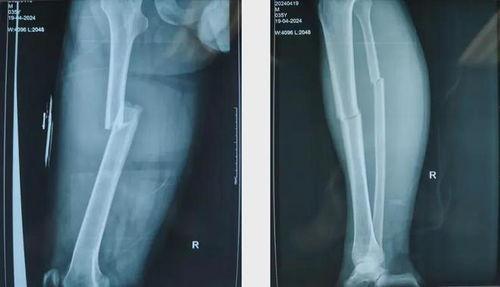

1. 股骨骨折:股骨骨折是常见的骨折类型,通常发生在老年人或交通事故中。